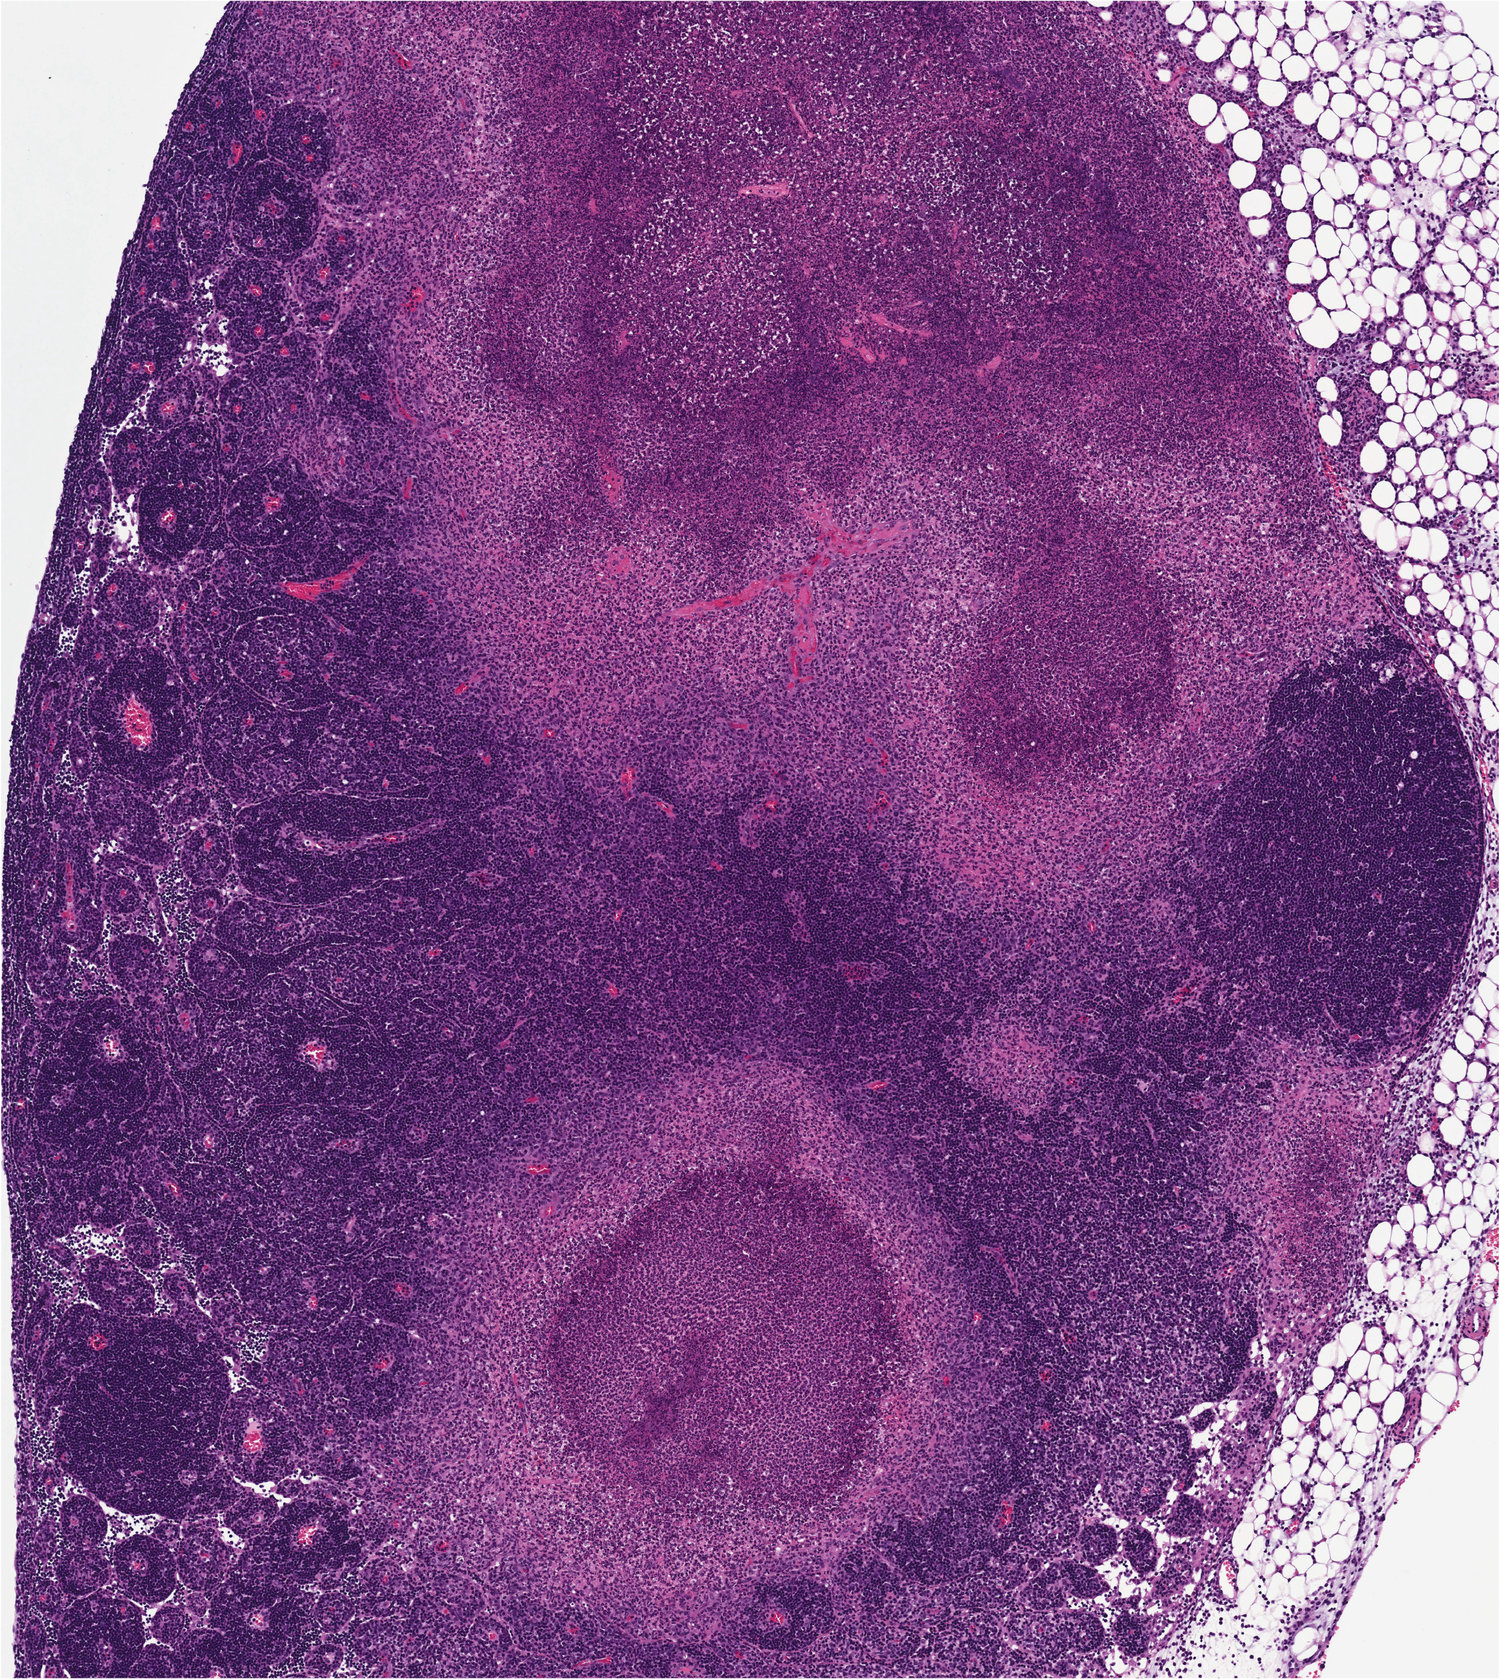

The immune system keeps a close eye on what’s going on inside the body, spotting foreign organisms before they’re able to cause any problems. However, pathogens have methods of counteracting this process, like emitting proteins that can interfere with immune cells’ signalling pathways. Brodsky’s group investigated Yersinia, the genus of bacteria that causes the black plague, which can prevent immune cells from signalling by injecting them with special proteins.

In the engineered mice, RIPK1 is unable to trigger apoptosis, a form of controlled cell death, when it detects Yersinia bacteria. As a result, the animals perished when they were exposed to the pathogens, even though they would normally be able to fight off the infection.

While it had previously been observed that RIPK1 can prompt cell death, this study offers up an explanation for why this is happening — other cells nearby are being warned of the pathogen’s presence. The researchers demonstrated that apoptosis induced by RIPK1 prompts the release of cyokines, the substances created by the immune system, by uninfected bystander cells. Without apoptosis, the cells can’t create the inflammatory response that saves them.